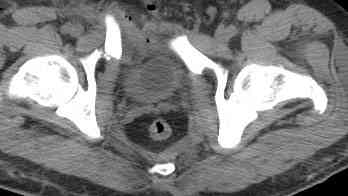

Уважаемые коллеги! опять вопрос по повреждению таза. Больной получил производственную травму 10 дней назад - удар балкой около 3 тонн в область верхней трети правого бедра и лона.

Был диагностирован перелом "типа бабочки" и повреждение уретры. Сделана цистостома. У насв отделении 3 дня. Имеется огромная флюктуирующая гематома с "галифе"-образной деформацией обеих бедер. Пнкционно эвакуировали в несколько приемов из подфасциальных полостей на бедрах около 3 литров геморрагического отделяемого с последующей эластической компрессией. При пункциях выявлено сообщение полостей на бедрах - видимо через поравннуюдиафрагму дна и полость таза - при удалении крови справа уменьшался объем левого бедра. Какой то активности проявялять покабоимся - аппаратная фиксация через отслоенные ткани представляется чреватой нагноением, открытая фиксация в условиях такой гематомы тоже не радует. Хотелось бы услышать ваше мнение

18.12. - отдельное спасибо еще раз А.В.Рункову- больного оперировали (А.В.Рунков) - произведен остеосинтез аппаратом - фиксация за крылья, два стержня в лонные кости и репозиция (почти полная) снимки будут чуть позже.

Дренировали отслойки на бедрах с их санацией. В правой ягодичной области сформировалась зона некроза. Больной "подвешен" за аппарат.